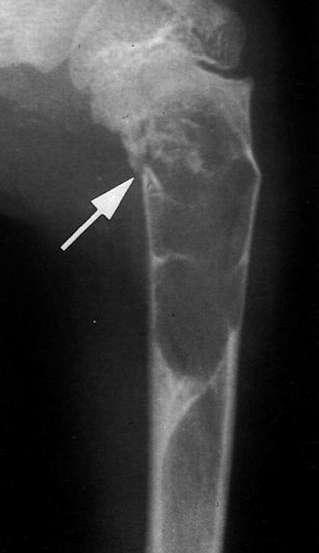

桡骨上段成骨型骨肉瘤:骨质增生硬化,并有骨膜反应,软组织肿块